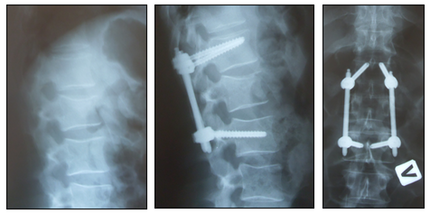

Рис. 3. Фиксация нескольких повреждённых сегментов позвоночника без существенной коррекции и реконструкции.

(Пациент с нестабильными повреждениями 2-х грудных позвонков, ушибом лёгких, двусторонним гидротораксом. В этих условиях трансторакальная, в том числе эндоскопическая, реконструкция передней колонны в ранние сроки сопряжена с риском гнойных осложнений).

Рис. 4. Фиксация нескольких повреждённых сегментов позвоночника с реконструкцией передней колонны.

Рис. 5. Редукция, перкутанная ТПФ и моносегментарный межтеловой спондилодез при травматическом спондилолистезе L-V позвонка.